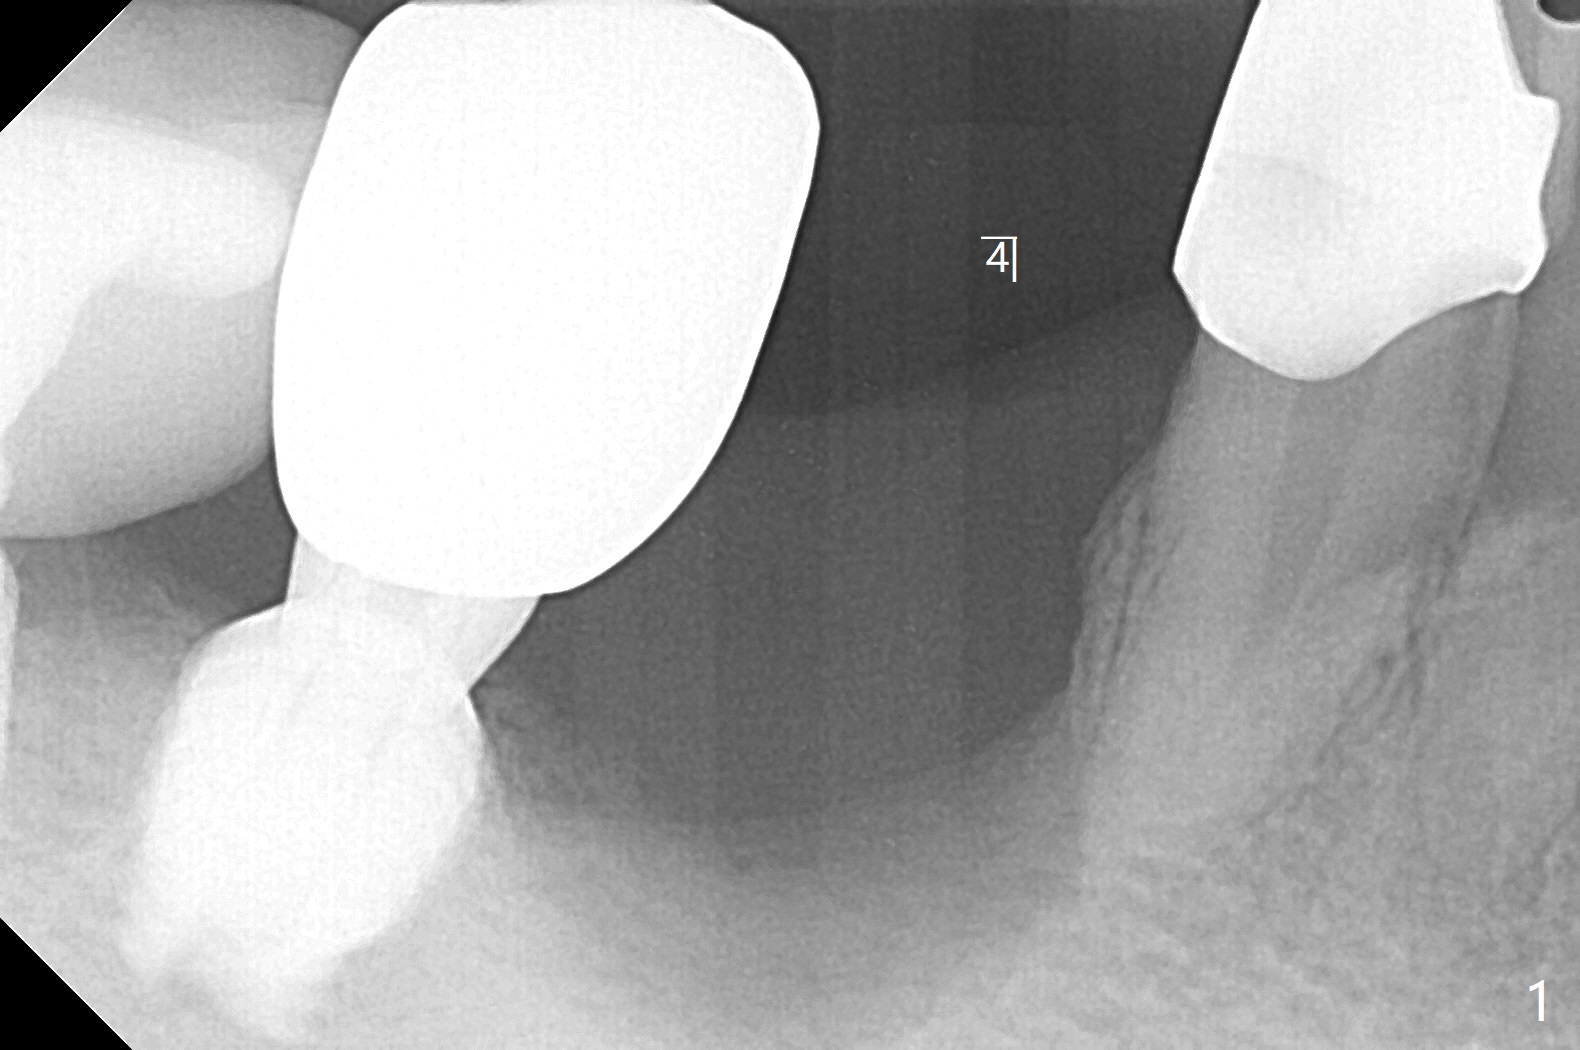

52岁男右下4植体脱落三天回到诊所(图一),植牙创尚未闭锁,顺着开口去除肉芽组织,冲洗,充填皮质骨骨粉(图二,三),颊侧骨板外形恢复(图四,五:*)。重新植入UF植体(5)颊侧还有薄颊侧骨板(图五:>),而6植体周围骨质吸收(图六),植骨好像有希望,植体还在牙槽骨范围,也有利于5植体生存。术后12天伤口愈合(图七)。尽管使用水枪,仍有6植体周围炎,需要治疗(图八)。由于右侧手术,病人不得不用左侧咀嚼,他认为左下4松动,无法挽救。术后3.5个月牙槽嵴和角化龈缩小(图九),需要切开使用导板。术后3.5个月骨粉高度明显下降(图十)。只能植入4x8.5毫米植体(图十一)。